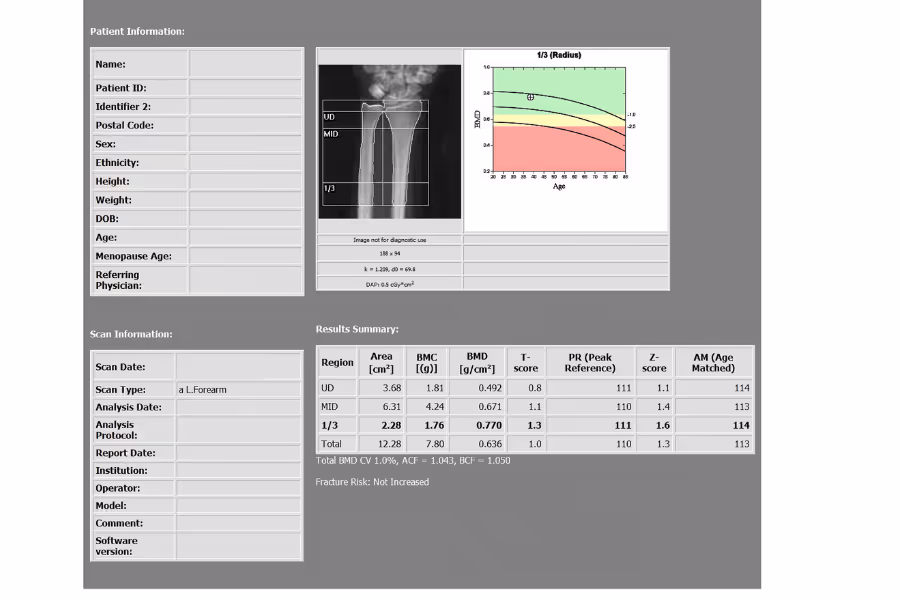

A DEXA scan (dual‑energy X‑ray absorptiometry) is a bone density test that uses a very low dose of X‑rays to measure how strong your bones are—most commonly at the hip and spine. The result helps estimate your risk of osteoporosis and fractures.

T‑score

Compares your bone density to a healthy young adult reference.

Z‑score

Compares your bone density to people your age/sex. This can be useful if you're younger or if there's concern about secondary causes of bone loss.

A physician or radiologist trained in bone densitometry reviews your scan and writes a report that typically includes: